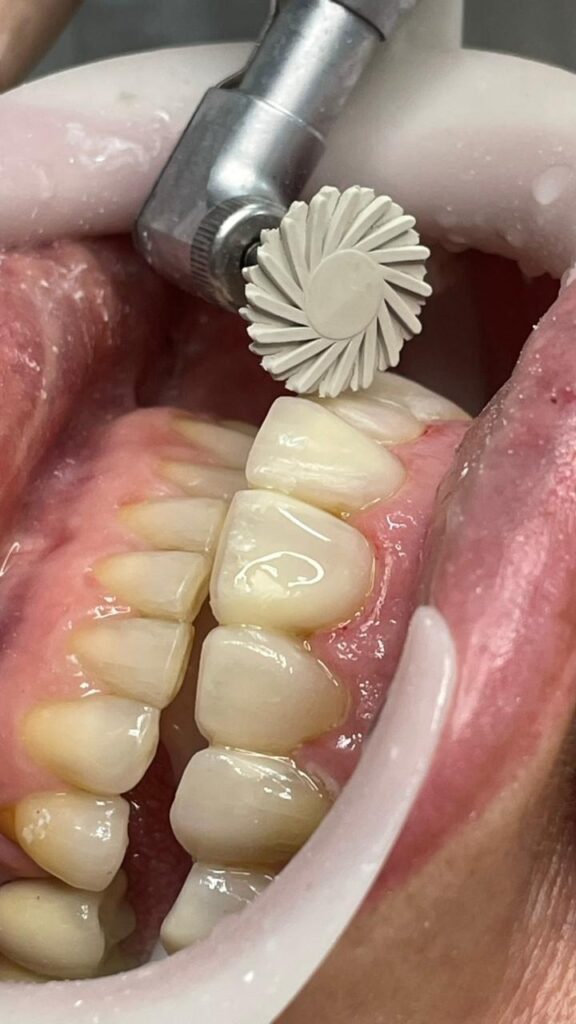

O procedimento clínico teve início com a remoção cuidadosa das facetas antigas com broca multilaminada em alta rotação (figura 6). Em seguida foi realizada a anestesia com o anestésico mepivacaína 2% com epinefrina 1:100.000 (DFL). Os dentes foram devidamente isolados com campo operatório absoluto, após o isolamento foi feita a lavagem da superfície com clorexidina 2%, seguido de ataque ácido fosfórico 37% por um período 15 segundos (MAQUIRA) e lavagem pelo mesmo período de tempo. Aplicação do sistema adesivo universal (FGM), fotopolimerizado por 20 segundos. Em seguida a confecção das conchas palatinas utilizando a resina trans (FORMA), (figura 7).

Figura 6: Remoção das facetas insatisfatórias

Após a escultura final, foi realizada a remoção do isolamento, checagem da guia canina, términos cervicais e ponto de contato, seguido do acabamento e polimento utilizando a baixa rotação com discos de lixa (TDV) com água. Dando sequência, utilizou-se pontas espirais JIFFY POLISHER (ULTRADENT), e por fim pontas Enhance, também em baixa rotação com pedra pomes e água, respeitando as áreas de sombra e espelho, etapas essenciais para o sucesso clínico e a longevidade das restaurações. O polimento adequado potencializou o brilho superficial, reduziu a adesão de biofilme e conferiu um aspecto natural à faceta, integrando estética ao conjunto dentário, conforme apresentados nas figuras 9 e 10.

Figura 9: Acabamento com disco de lixa.

Figura 10: Polimento com espiral abrasiva média.